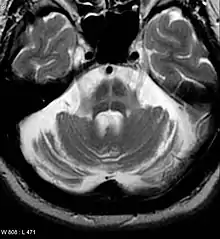

Imaging

Computed tomography (CT) scans of people with PD usually appear normal.[110] Magnetic resonance imaging has become more accurate in diagnosis of the disease over time, specifically through iron-sensitive T2* and susceptibility weighted imaging sequences at a magnetic field strength of at least 3T, both of which can demonstrate absence of the characteristic 'swallow tail' imaging pattern in the dorsolateral substantia nigra.[111] In a meta-analysis, absence of this pattern was highly sensitive and specific for the disease.[112] A meta-analysis found that neuromelanin-MRI can discriminate individuals with Parkinson's from healthy subjects.[113] Diffusion MRI has shown potential in distinguishing between PD and Parkinson-plus syndromes, as well as between PD motor subtypes,[114] though its diagnostic value is still under investigation.[110] CT and MRI are used to rule out other diseases that can be secondary causes of parkinsonism, most commonly encephalitis and chronic ischemic insults, as well as less-frequent entities such as basal ganglia tumors and hydrocephalus.[110]